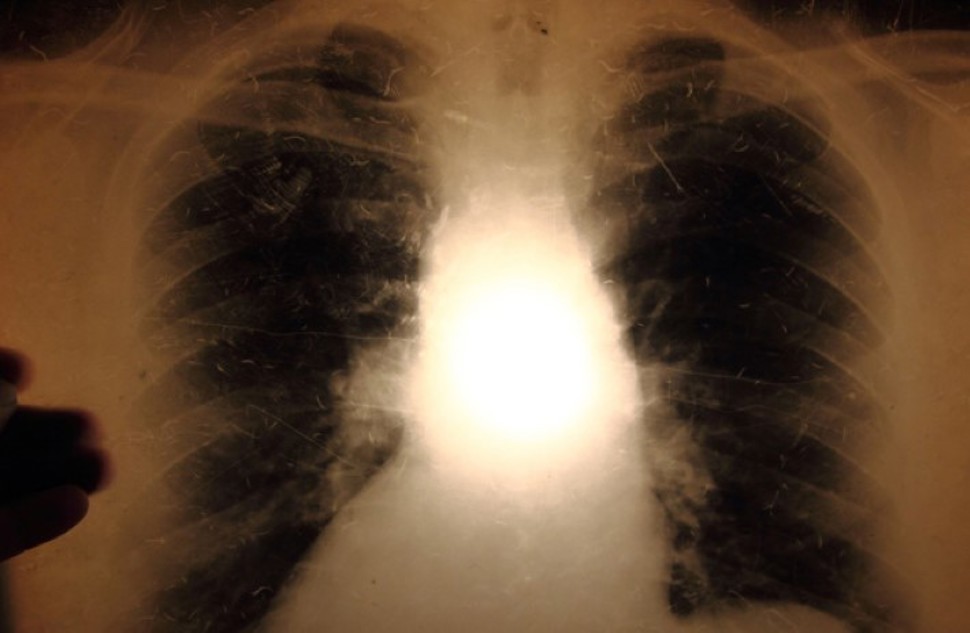

Tuberkulose

Fakta, statistikk, pasientinformasjon og veiledning for helsepersonell om tuberkulose.